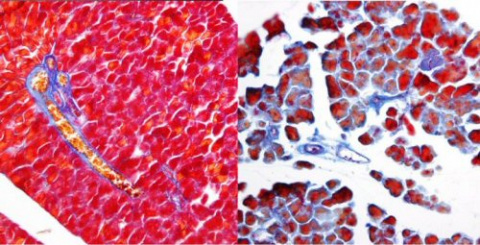

Bacterias de la especie Mycobacterium tuberculosis, principal culpable de la tuberculosis. (Foto: CDC)